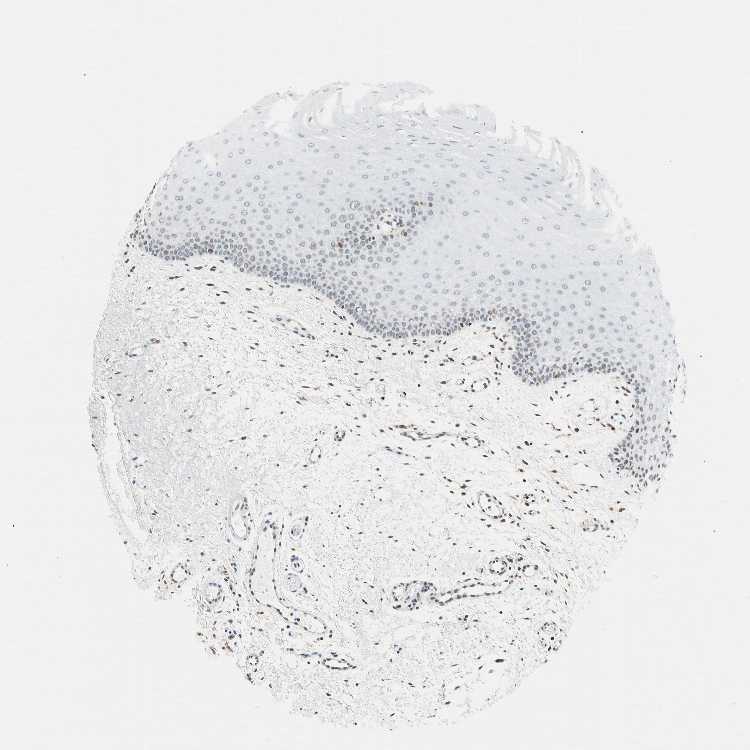

ORAL MUCOSA - Antibody stainingi

Antibody staining in the annotated cell types in the current human tissue is reported as not detected, low, medium, or high, based on conventional immunohistochemistry profiling in selected tissues. This score is based on the combination of the staining intensity and fraction of stained cells.

Each image is clickable and will lead to virtual microscopy that enables deeper exploration of all samples and also displays staining intensity scores, fraction scores and subcellular localization as well as patient and tissue information for each sample.

Antibody HPA007641Antibody CAB022464

Squamous epithelial cells Not detectedMedium